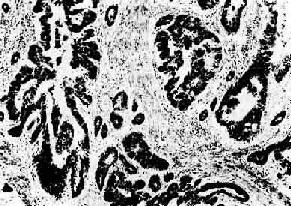

图7-14 乳腺硬癌

癌细胞呈条索状排列,间质丰富,由多量纤维组织构成